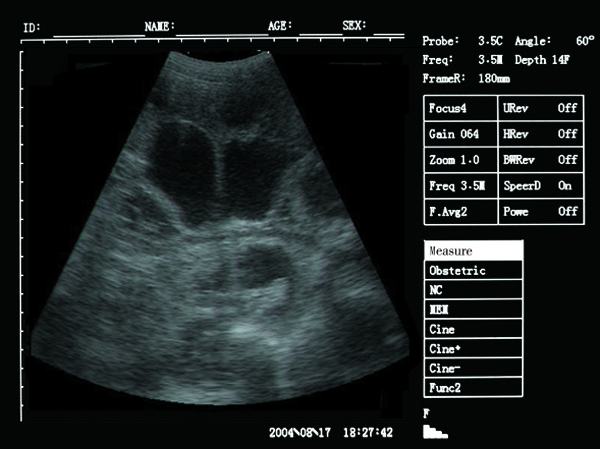

Scan results :